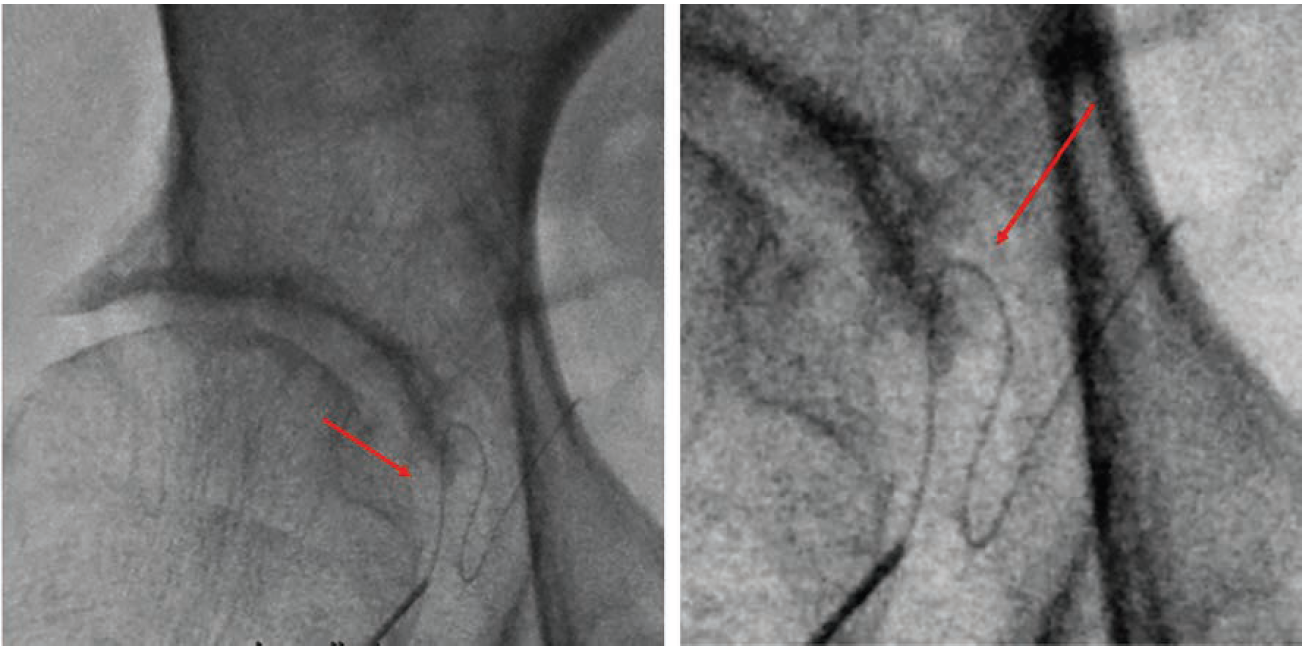

Figure 2 shows an injury to the IE that occurred due to 18-gauge needle laceration, which led to serious retroperitoneal bleeding (note yellow arrow of bladder displaced to the left from massive retroperitoneal bleed) that was only noted after the patient gradually became hypotensive during the case. Figure 3 shows an example of through-and-through sheath insertion of the IE that occurred during venous access that was properly managed with coils that extend distal and proximal to the hole. Of course, it goes without saying that proper access technique with a combination of fluoroscopy AND ultrasound could have prevented these incidents in the first place.

Courtesy of Dr. Zoltan Turi.

Of course, the way to help avoid the IEA is ultrasound and fluoro during access. Ultrasound imaging is better at preventing low puncture, fluoro helps to avoid high puncture. Because micropuncture needles use small straight wires, it is easy to inadvertently engage the IEA during access or on the lateral side of the external iliac, the lateral circumflex of the hip. It is best to fluoro after the wire advance but before advancing a dilator; the pattern of the wire in the branch vessel instead of external iliac engagement is usually easy to recognize (Figure 5). Then, before anticoagulation, I would always do a sheath angiogram to look at puncture location and also for dye extravasation either from a branch vessel like the IEA, or from inadvertent puncture of the external iliac higher up. Even if the sheath entrance was below the inguinal ligament, a perforation may have occurred, caused by a dilator tip or wire perforating a tortuous external iliac artery. Doing the sheath angiogram at the beginning of the case allows you to stop before anticoagulation. If at the end of the case you suspect retroperitoneal hemorrhage, you can take advantage of the incidental cystogram that is already there (if you have given any meaningful amount of dye and the case lasted long enough) and look for compression (the “bladder sign”3), (Figure 6).